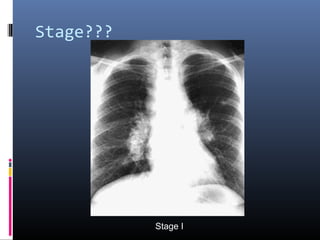

Stage???

Stage II disease

• #10 Sarcoidosis, thoracic. Stage II disease. Chest radiograph in a 36-year-old woman shows mediastinal lymph node enlargement and bilateral pulmonary opacities.

• #14 Stage II sarcoidosis. Posteroanterior chest radiograph demonstrates massive bilateral hilar lymphadenopathy as well as bilateral parenchymal infiltrates. Note the predilection for mid and upper lung zones.